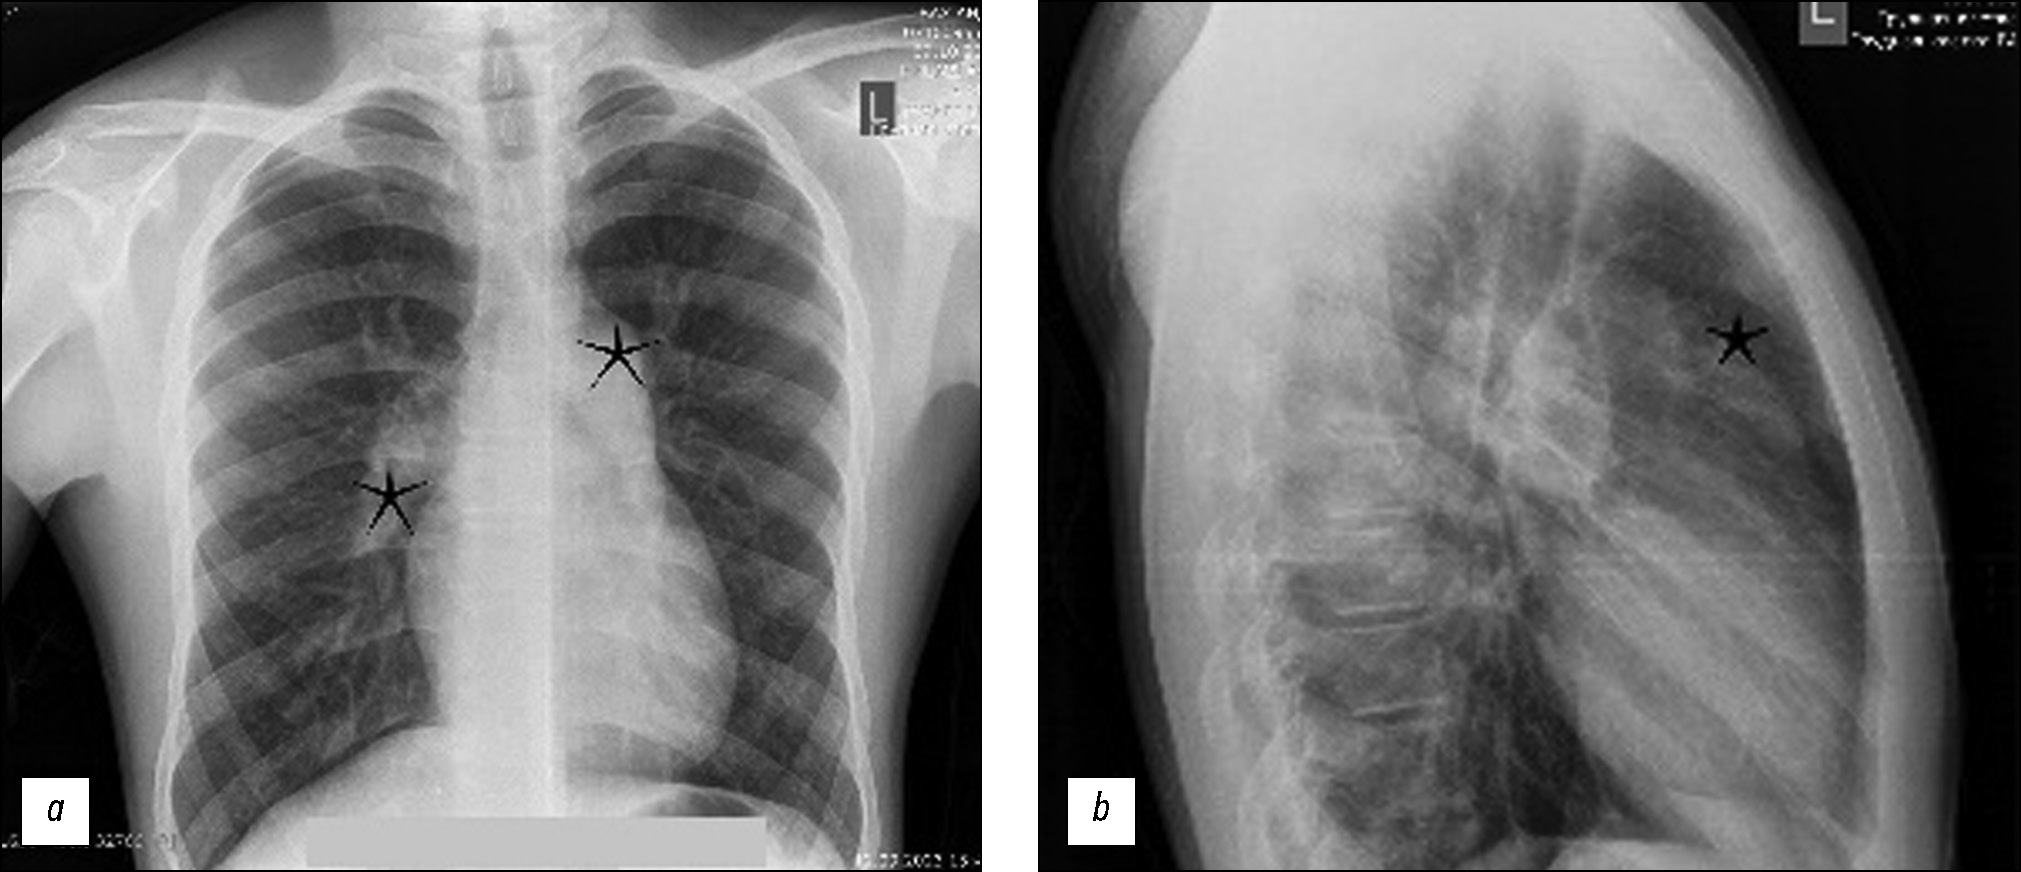

Pulmonary artery pseudoaneurysm in a young man with pulmonary hypertension on computed tomography angiography

Abstract

Pulmonary artery aneurysms and pseudoaneurysms are uncommon anomalies; however, their associated morbidity underscores the importance of recognizing them. Herein, we present a clinical case involving a 15-year-old male patient who presented at our clinic with complaints of hemoptysis. Upon diagnosis, a left lung aneurysm was found. Subsequent computed tomography angiography and intervention on the pulmonary arteries confirmed the presence of pulmonary artery aneurysms, elucidating that the hemoptysis was caused by the rupture of the aneurysm. The intervention on the pulmonary artery further confirmed the diagnosis. Early detection and management of pulmonary artery aneurysms are crucial, particularly in young patients, as timely intervention can prevent severe complications and improve patient outcomes. Raising awareness of these vascular abnormalities and promptly addressing them through appropriate diagnostic measures and interventions can help healthcare providers effectively mitigate the potential risks associated with pulmonary artery aneurysms, thereby enhancing patient care and prognosis.

623-631